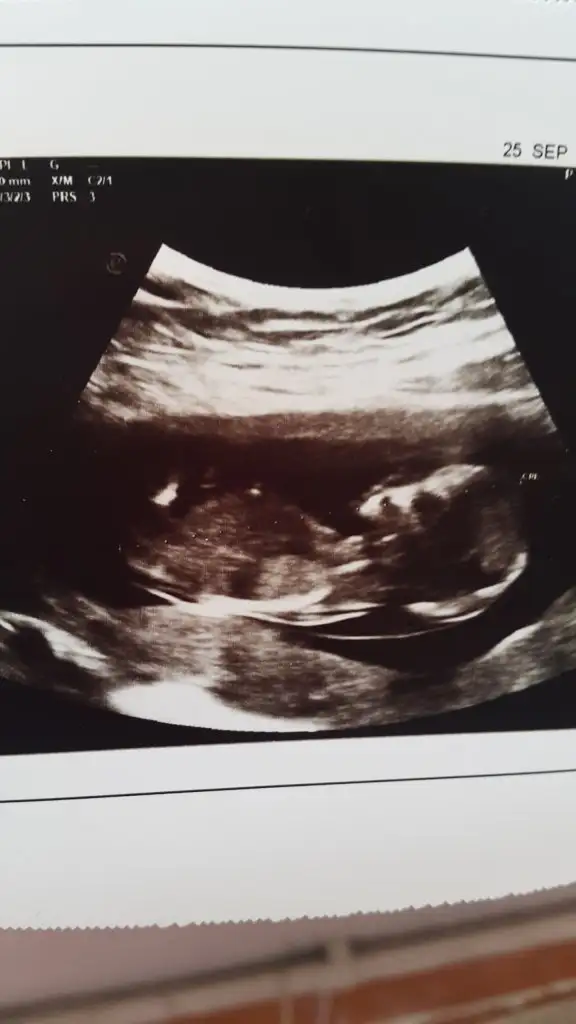

Kaç haftalık USG hiç net değil sanki Küçük nub için 11 12 13 haftalar olmalı

Tam dik değil paralelde değil yüzde verirsem sanki %70 kız gibi gibi başka usgde paylaşın 11 12 13 haftalar olmalıEki Görüntüle 2696428 bende tahmin alabilir miyim